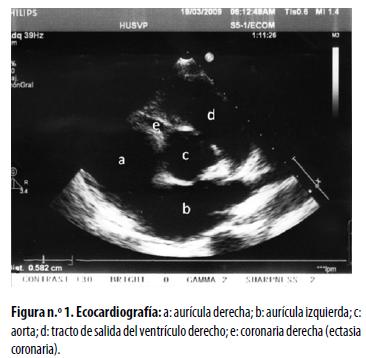

La ecocardiografía practicada en ese momento demostró lo siguiente: coronaria derecha con diámetro de 5 mm en su origen (puntaje Z: 5); coronaria izquierda con diámetro de 5,4 mm en su origen (puntaje Z: 4,14). No se encontraron trombos, ni aneurismas, ni dilatación de las cavidades cardíacas. Estos hallazgos fueron interpretados como ectasia coronaria (figura n.° 1). En vista de este resultado, se inició tratamiento intravenoso con gammaglobulina estándar, a razón de 2 g/kg, en dosis única, y ácido acetil–salicílico en dosis de 35 mg/kg/día. El paciente tuvo mejoría muy notoria en los dos días siguientes al comienzo del tratamiento y se lo dio de alta en buen estado general. Las revisiones posteriores en la consulta externa constataron gran mejoría clínica subjetiva y objetiva, aunque persistió la inyección conjuntival. En la tabla n.° 1 se resume la evolución de su enfermedad.